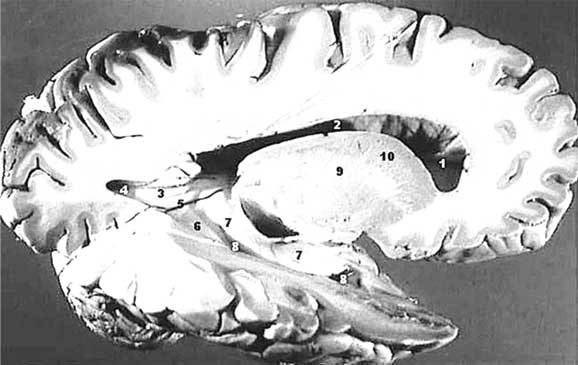

Но если есть развитая нервная система, то должны быть и эмоции, не так ли? Вопрос о том, какие эмоции может испытывать тринадцатинедельный плод, довольно спорный, но давайте допустим, что он их все же испытывает и выражает свои переживания гримасами и движениями. Кора головного мозга уже сформировалась и что с того, если она пока еще гладкая, без извилин? Борозды, «нарезающие» кору головного мозга на извилины, увеличивают ее площадь, то есть – повышают количество нервных клеток, которые располагаются строго на периферии, тонким слоем. Толщина этого слоя, называемого «серым веществом» за свой цвет, колеблется на разных участках от полутора до четырех миллиметров. Под серым веществом лежит массивный пласт белого вещества, образованного волокнами нервных клеток. Белое вещество не генерирует нервных импульсов, оно их только проводит.

Почему бы природа вместо того, чтобы нарезать в коре борозды, не увеличила толщину серого вещества? Проводящая система могла бы быть и покороче, от этого ничего бы не изменилось. Но, видимо, есть какие-то, пока еще неведомые нам причины, по которым нервным клеткам нужно располагаться в коре тонким слоем. Вот и приходится идти на ухищрения, чтобы увеличить площадь поверхности коры втрое. Неплохой, надо сказать результат. Таким образом, пока кора больших полушарий остается гладкой, высшая нервная деятельность, та самая, которая делает нас разумными созданиями [28], осуществляется в треть своей мощности, но для начала и этого достаточно. Кстати говоря, значение имеет не только количество нервных клеток в коре головного мозга, но и количество связей между ними. Чем больше связей образуют клетки, тем выше функциональные возможности коры.

Иллюстрация к книге — Твоя жизнь до рождения: тайны эволюции человека [i_049.jpg]

Серое и белое вещества коры больших полушарий